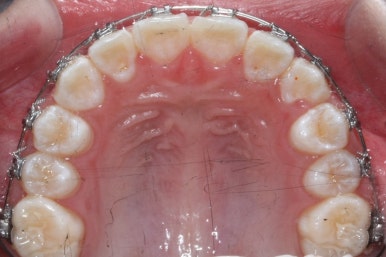

첫 장치 부착한 모습입니다.

아직 유치가 몇 개 남아있기에 장치가 전체적으로 부착되지 않습니다. 우선 앞니 4개만 먼저 치열을 맞추고 위쪽 어금니는 후방 이동을 해주면서 교합을 맞추며 덧니가 내려올 공간을 확보합니다.

연산동덧니교정 키다리아저씨치과에서는 메탈 장치를 사용했습니다.

많이 사용 되는 클리피씨 장치 등의 세라믹 보다는 아이가 양치하기 쉬운 부피가 작고 비용도 덤으로 낮은 메탈장치를 사용했습니다.